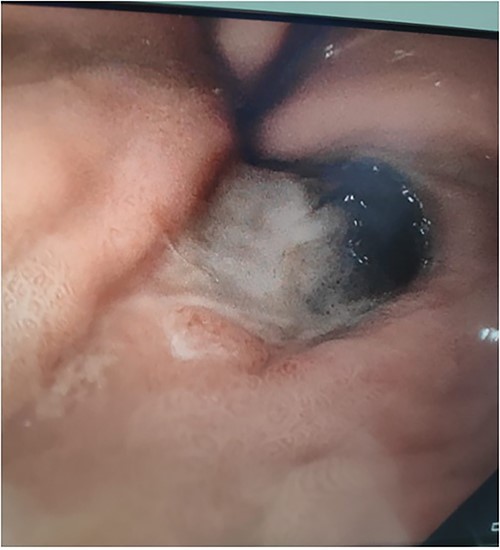

A 71-year-old female presented to a rural hospital with generalised abdominal pain and fevers in the context of a fall 3 days prior on a background of a myeloproliferative disorder, type 2 diabetes mellitis, cerebrovascular accident (CVA), chronic kidney disease and hypertension. The patient was tachycardic, febrile and had a peritonitic abdomen on examination. A computed tomography (CT) scan demonstrated a subcapsular splenic haematoma and haemoperitoneum. Urgent laparotomy revealed a sub-phrenic abscess and infected splenic haematoma for which uncomplicated splenectomy was performed. The postoperative course was initially uncomplicated with the patient tolerating diet, opening bowels and mobilising appropriately. Day 3 postoperatively, the patient developed burning central chest pain for which cardiac investigations were unremarkable. The patient received two units of packed red blood cells for a haemoglobin of 82 and intravenous proton pump inhibitor. The patient subsequently had a 250-ml episode of haematemesis and became haemodynamically unstable. Urgent upper gastrointestinal endoscopy demonstrated oesophageal necrosis from 20 cm from the teeth to the proximal margin of the gastro-oesophageal junction, diffuse bleeding from the distal oesophagus and adherent clot at the gastric fundus. The patient was transferred to a tertiary centre where repeat endoscopy demonstrated oesophageal necrosis and a well-circumscribed area of gastric fundus necrosis (see Figs 1–3) at the site of the adherent clot. Oesophageal biopsy demonstrated herpes simplex virus (HSV) 1-associated oesophagitis. Post-endoscopy the patient developed renal failure and failed extubation in intensive care. Given the multiple comorbidities of the patient and declining functional status prior to admission the family felt further invasive measures would not be in her best wishes. The patient was transitioned to comfort care and passed away the following day.

Upper gastrointestinal endoscopy image demonstrating sparing of the gastro-oesophageal junction.